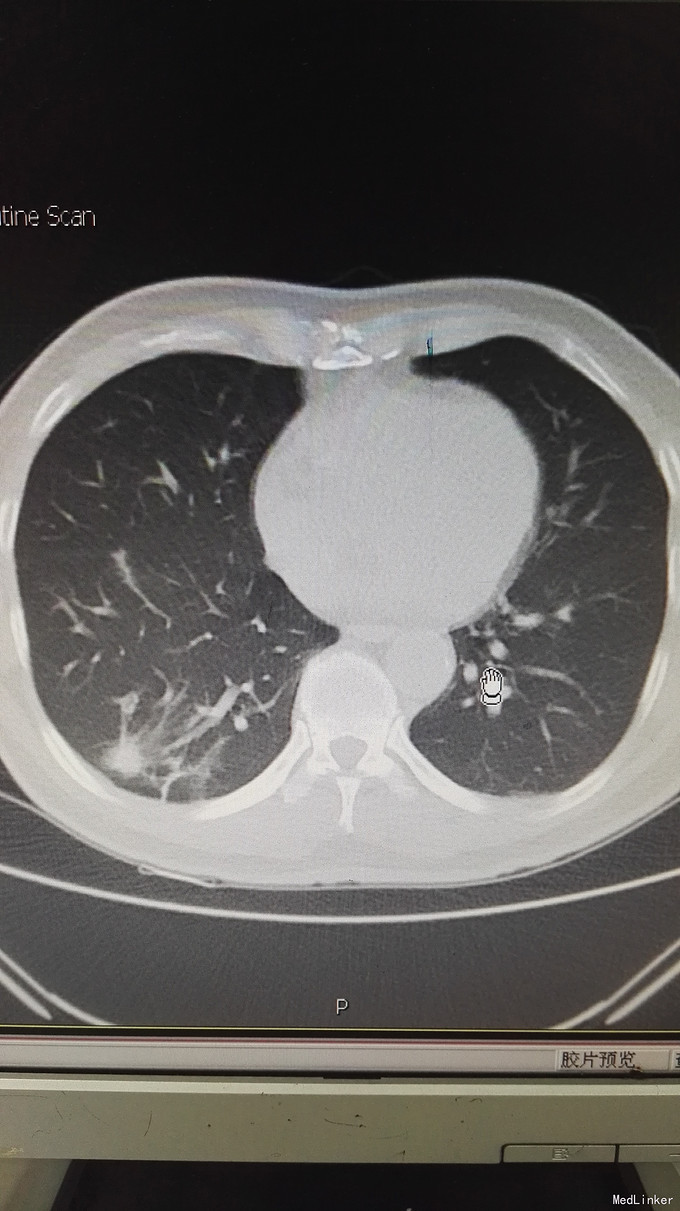

患者男,65岁,退休人员,因体检发现双肺阴影 半月入院。无不适症状。不嗜烟酒,有高血压、糖尿病史。

查体未见异常。 辅助检查:血常规、肿瘤指标、免疫指标、肝肾功能、痰涂片均未见异常。PCT、CRP不高。CT如图:右肺下叶多发斑片状影,左肺上叶蛇段、下叶少许条索状影,考虑双肺慢性炎症。

诊断:双肺阴影查因:肺炎? ; 高血压病 ;2型糖尿病 治疗,目前先进行抗感染及控制血压、血糖处理。